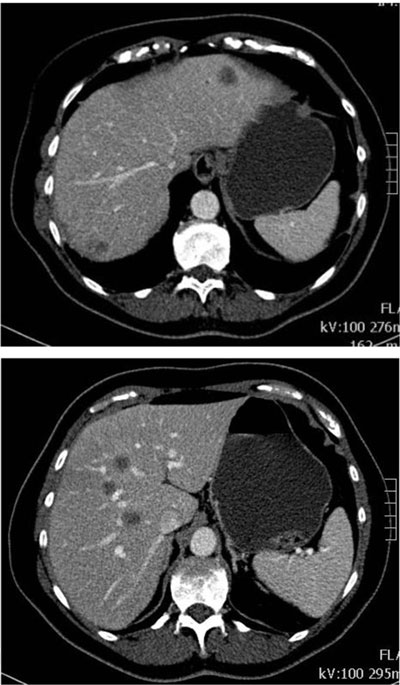

Figure 1

Contrast-enhanced CT abdomen in the portal venous phase: multiple focal low-attenuation nodular lesions in the liver.